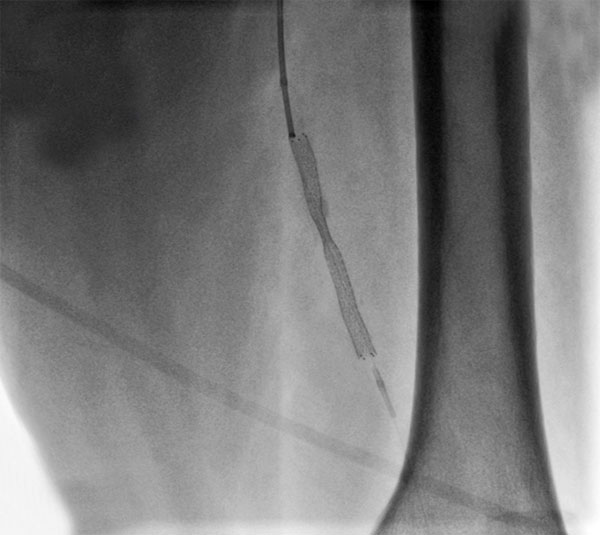

Рис. "Завершение эндоваскулярного этапа - контрольная ангиография: поверхностная бедренная артерия без остаточного стеноза, магистральный кровоток без препятствий, стент раскрыт полностью."